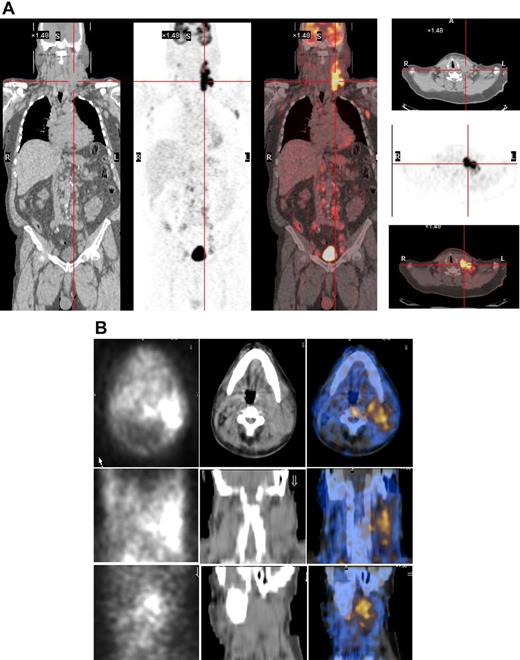

131I-L19SIP SPECT-CT images and 18F-FDG PET scans

As the radiopharmaceutical 131I-L19SIP contains the very same binding moiety, L19, used for immunohistochemical determination of ED-B FN in lymphoma samples, this radiolabeled agent maintains both high affinity for the target antigen and binding properties typical to other L19 fusion proteins.35 In the patient with advanced SLL NHL, transaxial, coronal, and sagittal 131I-L19SIP SPECT-CT images demonstrated selective ED-B FN targeting in a palpable, enlarged lymph node conglomerate in the left cervical region, which corresponded to high 18F-FDG uptake on the baseline PET-CT scan (Figure 5). The absorbed dose in the target lesion was estimated at approximately 18 Gy, whereas it was 0.99 Gy and 0.42 Gy in the bone marrow and kidney, respectively. The patient was subsequently treated with a dose of 5.55 GBq 131I-L19SIP. He achieved disease stabilization at 1 month after therapy with the sum of involved lymph node diameters unchanged from baseline (403 vs 417 mm; baseline to 1 month after treatment). However, this patient experienced no clinical benefit from 131I-L19SIP radioimmunotherapy and went off study to receive palliative treatment.

131I-L19SIP uptake in lymphoma lesions in a patient (NHL1) with SLL NHL. (A) 18F-FDG PET scans demonstrate intense glucose metabolism in multiple enlarged lymph nodes, particularly in the left latero-cervical region. Coronal images are shown in the left panels and transaxial images of the cervical regions are displayed in the right panels. (B) The same patient received an intravenous infusion of 185 MBq and, subsequently, 5.55 GBq 131I-L19SIP. Transaxial, coronal, and sagittal SPECT-CT images of the cervical regions (first, second, and third rows, respectively) were acquired 8 days after the dose of 5.55 GBq. Left column shows scintigraphic images; central column, CT images; and right column, CT-scintigraphy fused images.